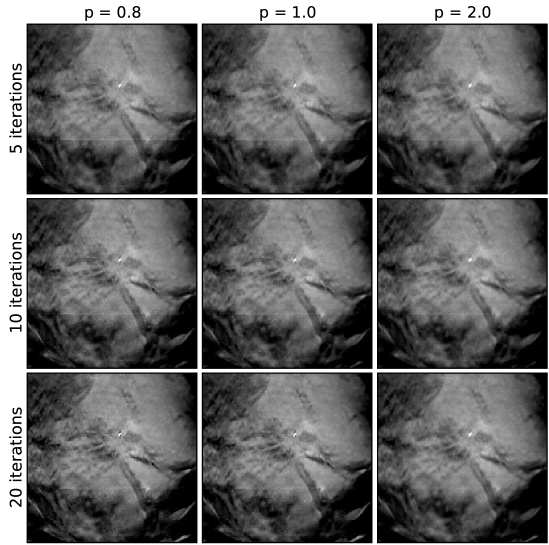

V.6 Case 3: spiculated mass in a dense breast

Finally, we present a case with a spiculated mass in dense breast tissue. It is precisely this type of case which DBT was developed for; by removing some of the interference of the overlapping structures such masses may be more conspicuous in DBT images than in standard mammographic projection imaging. The EM images are shown in Fig. 13, and the ASD-POCS images are shown in Figs. 14, 15, and 16. As with the previous mass case, there may be some advantage to image-reconstruction with ASD-POCS at low due to the fact that edges are enhanced. But the advantage is not as clear cut as it is with microcalcification imaging. Any advantage in mass imaging needs to be demonstrated by task-based image quality evaluation.

With this case, under-regularization, at large , tends to yield linear artifacts in the image. Actually, similar lines appear for the other cases in the first two iterations of ASD-POCS, but the quickly disappear and are gone by the fifth iteration. These lines, for the present case, are likely due to a slight system misalignment or patient motion. This case reveals the control afforded by the parameter in the ASD-POCS algorithm. It is easy to select a value of small enough to wash out the linear artifacts without severely blurring the underlying features of the image.